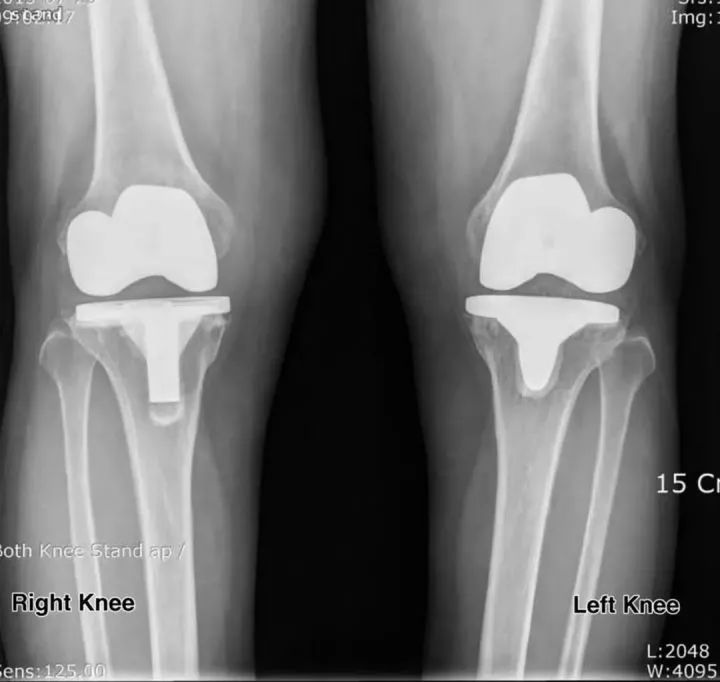

如今,醫(yī)學上開始利用氧化鋯陶瓷與塑料脛骨組件相結合的方式,代替了其他膝關節(jié)置換中使用的金屬托盤和塑料部件。實驗表明,這種新型膝蓋不但可以維持20-25年,大大超過鈷鉻合金和聚乙烯假體有效的15-20年,還可以對新組合進行自潤滑,從而實現(xiàn)更順暢,更輕松的鉸接。

這種材料的另一個重要特征是它具有生物相容性,這意味著患有鎳過敏并且不能使用鈷鉻合金制成的膝蓋假體的人(因為鎳是鈷鉻合金的一種成分)。由于不含鎳,氧化鋯假體徹底消除了鎳過敏患者的風險。